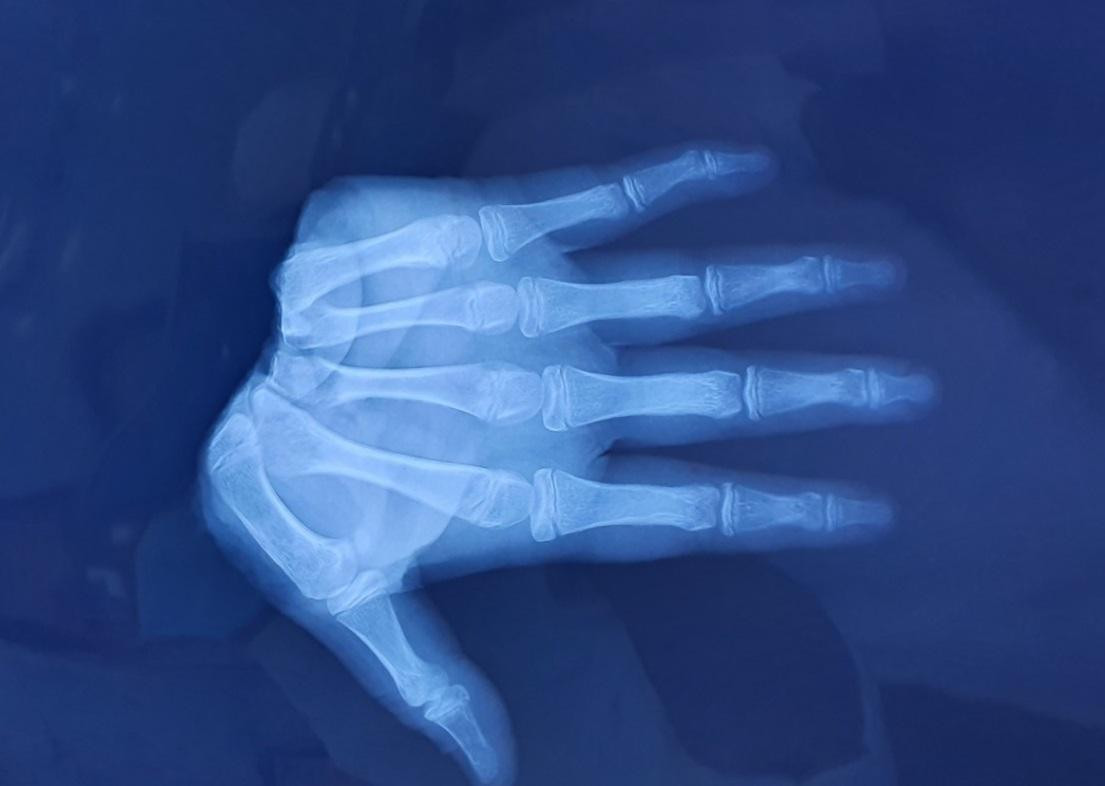

| Hình ảnh kiểm tra bàn tay đứt lìa của bệnh nhân trước khi thực hiện vi phẫu |